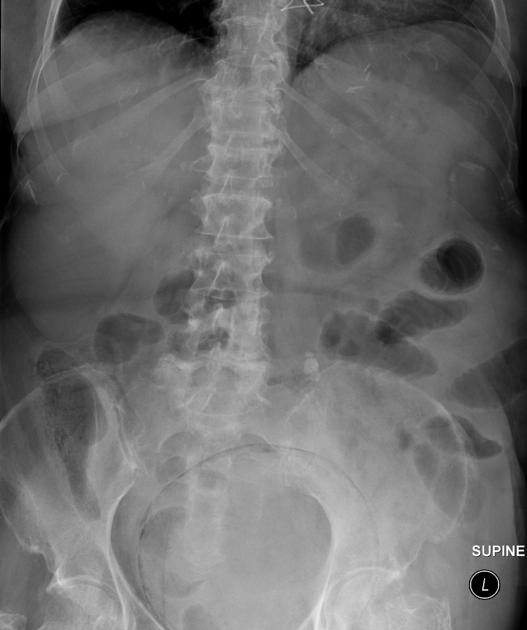

• Khí trong bàng quang

Viêm bàng quang sinh hơi (Emphysematous cystitis)